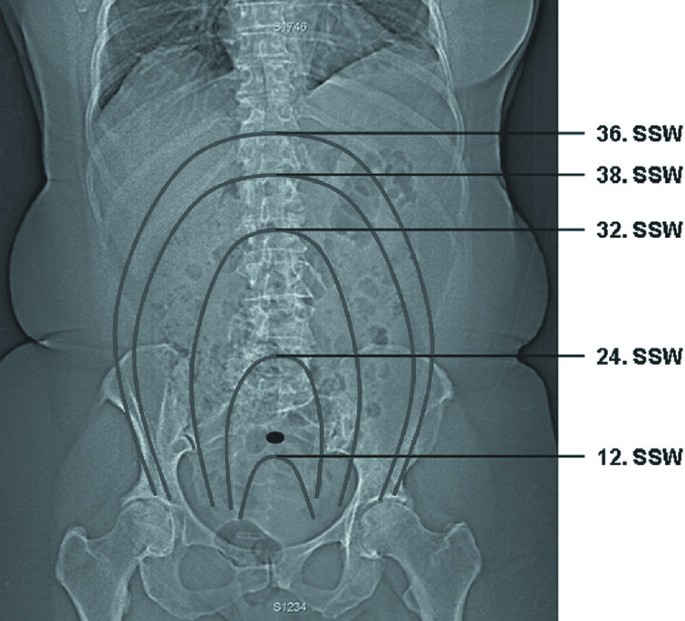

CT vor der Schwangerschaft: Höheres Risiko für Fehlgeburt?

Aktuelle Studie zeigt einen Zusammenhang zwischen einer Computertomographie und einem erhöhten Risiko für Fehlgeburten sowie für Fehlbildungen. Experten kritisieren das Studiendesign.